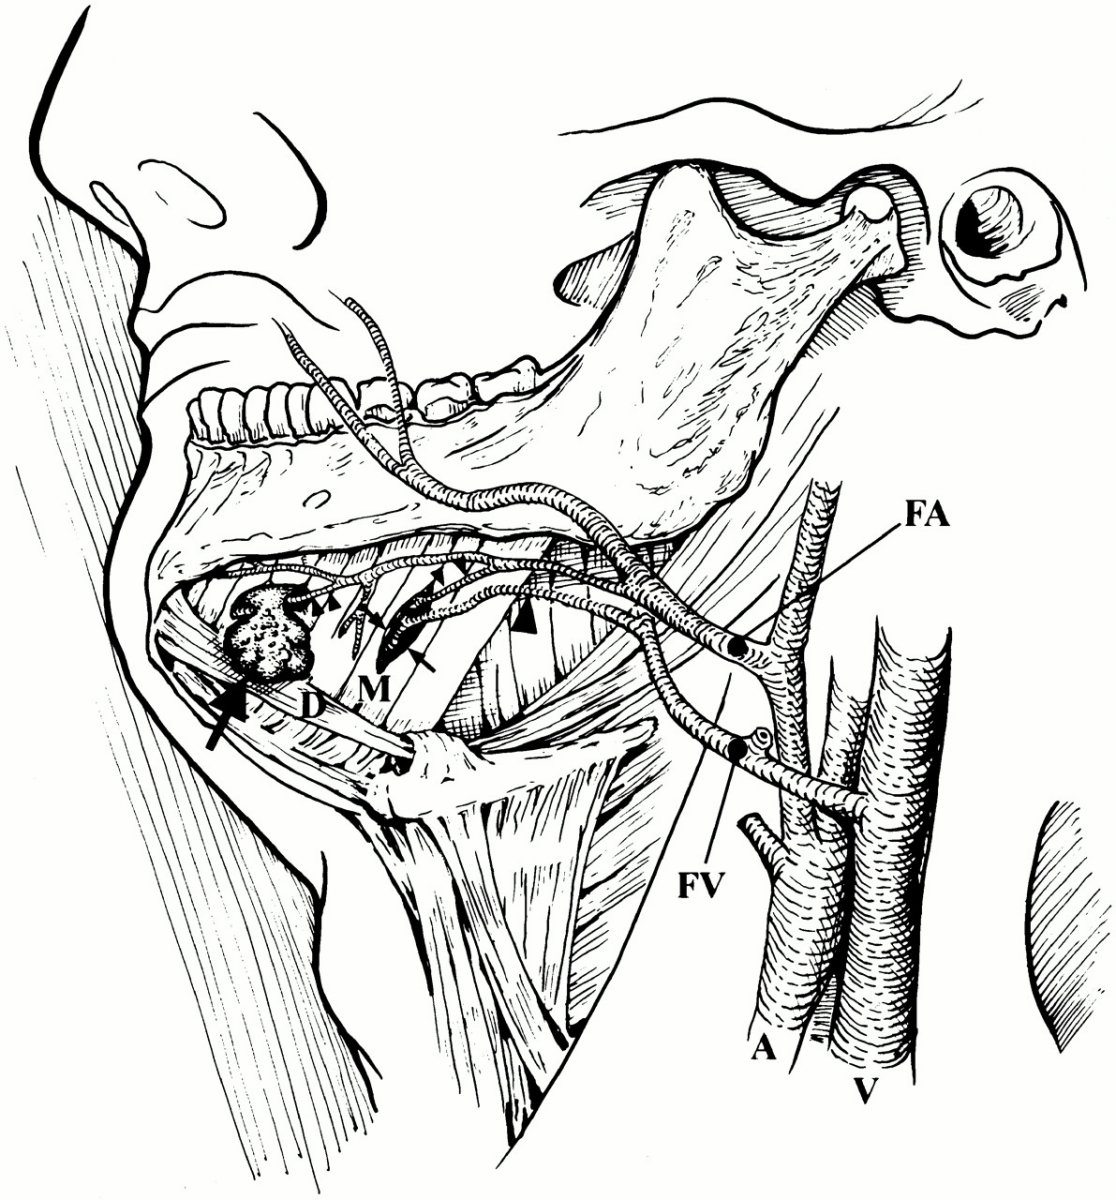

I did some plain research on teeth about the structure and some unusual silhouette deture.